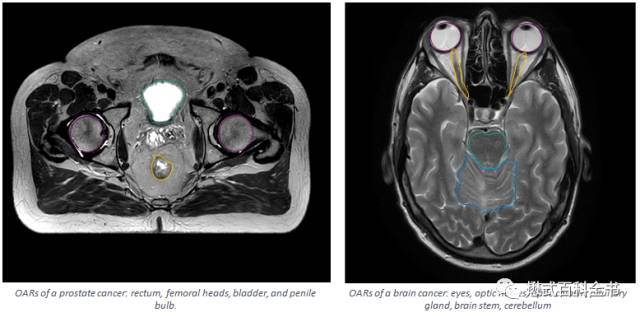

OARs(Organs At Risk), 危急器官:指在放射治疗中有可能暴露在射线中地器官。